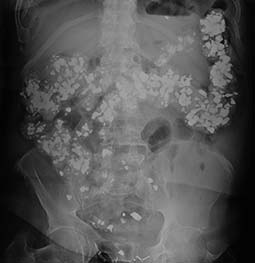

Imaging studies

These are done to identify the ingested materials as well as to treat the gastrointestinal complications of pica:

- Abdominal x rays

- Barium studies of the upper and lower gastrointestinal (GI) tracts

The studies may be repeated at regular intervals to track changes in the location of ingested materials.